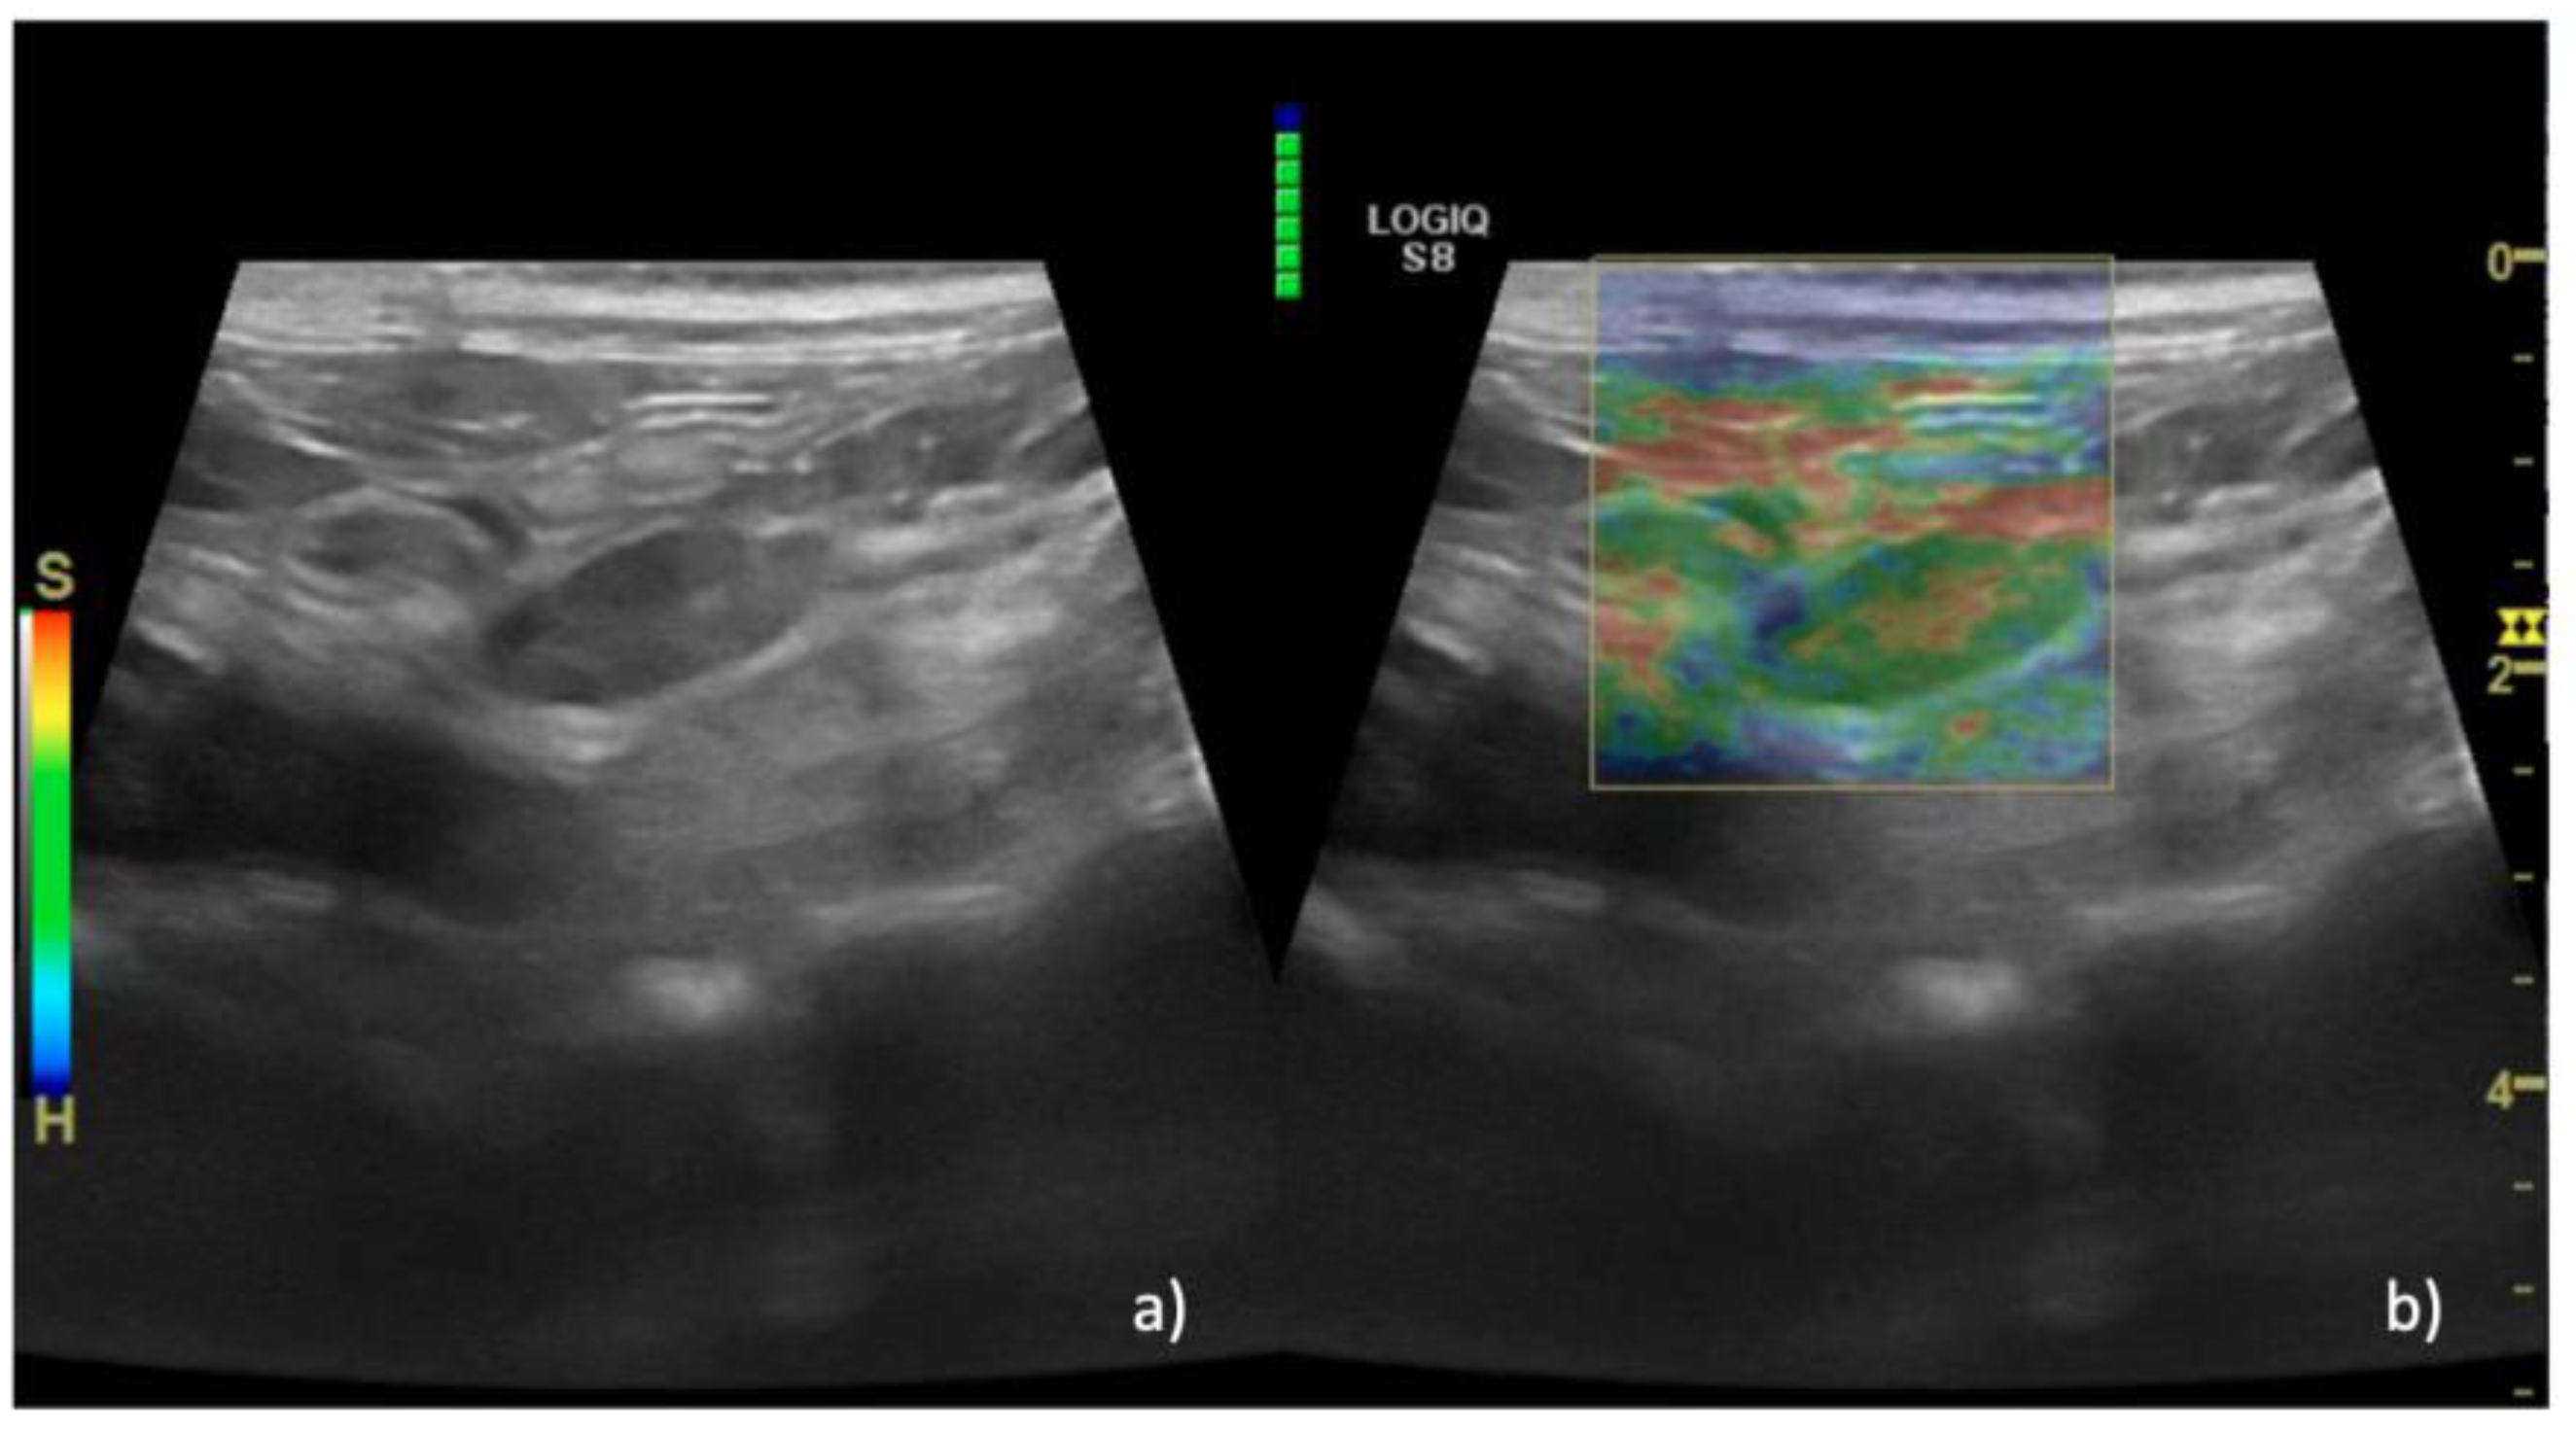

3. Results

| Sonoelastography | ||||

| EP | 1 n = 15 (36%) | 1 n = 0 | 1 n = 0 | |

| 2 n = 14 (35%) | 2 n = 0 | 2 n = 2 (4%) | ||

| 3 n = 11 (29%) | 3 n = 0 | 3 n = 15 (36%) | ||

| 4 n = 0 | 4 n = 0 | 4 n = 24 (58%) | ||

| 5 n = 0 | 5 n = 6 (100%) | 5 n = 1 (2%) | ||

| Median (IQR) | 2 (1–3) | 5 (5–5) | 4 (2–5) | 0.01 |

| SR, Median (IQR) | 0.5 (0.1–0.9) | 1.8 (1.5-2.2) | 0.7 (0.1–1.6) | 0.01 |